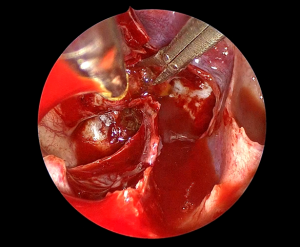

脳神経外科